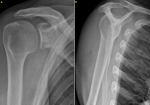

Case 1: X-rays showed osteolysis around proximal screw which was not bi-cortical. There was no geode around distal screw which was bi-cortical. There was no sign of omarthrosis (Figure 1). Computed tomography (CT) scan showed complete osteolysis of the coracoid bone block. Major geode was visible around proximal screw flush with glenoid articular surface communicating with joint through a thin opening. Volume of the bony defect was 8.3 cm3 (Figure 2).

Case 2: X-rays showed osteolysis around screw which was not bi-cortical. There was no sign of degenerative arthroplasty. Ultrasound was performed and showed no rotator cuff damage. CT scan revealed complete lysis of coracoid bone block. There was a geode around screw flush with glenoid articular surface. The volume of the bone defect was 2.2 cm3 (Figure 3).

Figure 2: (A,B,C) CT scan of right shoulder; axial, coronal and sagittal slices, joint communication

Figure 3: (A,B,C) CT scan of right shoulder; axial, coronal and sagittal slices